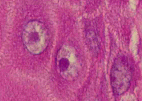

標本6

標本6の説明